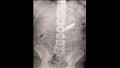

وأوضح الدكتور غنيم أن وحدة الطوارئ استقبلت مريضًا في العقد الرابع من العمر يعاني من وجود هاتف محمول داخل بطنه بعد أن ابتلعه بطريق الخطأ قبل 5 شهور. وتم إجراء الفحوصات الطبية اللازمة، بما في ذلك أشعة على البطن التي أكدت وجود الهاتف في المعدة. وبعد إجراء منظار استمر لمدة ساعة، تم استخراج الهاتف بنجاح، وخرج المريض من المستشفى بعد استقرار حالته الصحية.